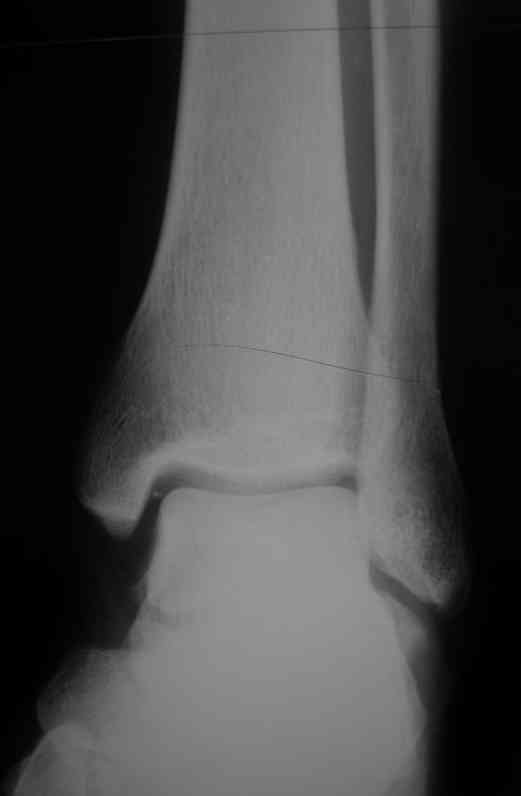

Уважаемые коллеги. Хотелось бы услышать ваше мнение по следующему случаю Обратился больной 23 года, травма 4 месяца назад - закрытый перелом наружной, внутренней лодыжки правой голени. Лечился консервативно, гипсовой иммобилизацией 8 недель, после снятия последней прошел курс восстановительного лечения. Беспокоят боли в области правого голеностопного сустава больше в проекции внутренней лодыжки, к вечеру. Отечность области сустава при физических нагрузках.Походка не изменена. Контуры правого голеностопного сустава сглажены. Имеется вальгусная установка правой пяточной кости. Объем движений в голеностопном суставе подошвенное / тыльное сгибание 50/0/80, безболезненные. Посоветуйте что делать в данной ситуации. Мне видится следующий вариант решения данной деформации: Восстановление нормальной анатомии голеностопного сустава - остеотомия малоберцовой кости и внутренней лодыжки, удалить все рубцы из области дистального межберцового синдесмоза, восстановить длину и устранить ротационное смещения наружной лодыжки.( встанет ли таранная кость на место?), фиксация наружной лодыжки пластиной, внутренней - винтами, дистального межберцового синдесмоза винтом. ЭОПом не располагаем. Что вы посоветуете? Где могут быть - технические трудности, <подводные камни>.

P.S. На боковой проекции таран выглядит несимпатично. Может быть изза качества снимка?

План вполне здравый. Но... Такое впечатление, что после устранения подвывиха суставные поверхности уже могут быть неконгруэнтны все равно.

То ли там есть импрессия в наружном отделе суставной площадки tibia, то ли не знаю что... IMHO не сильно криминальым выглядит и вариант